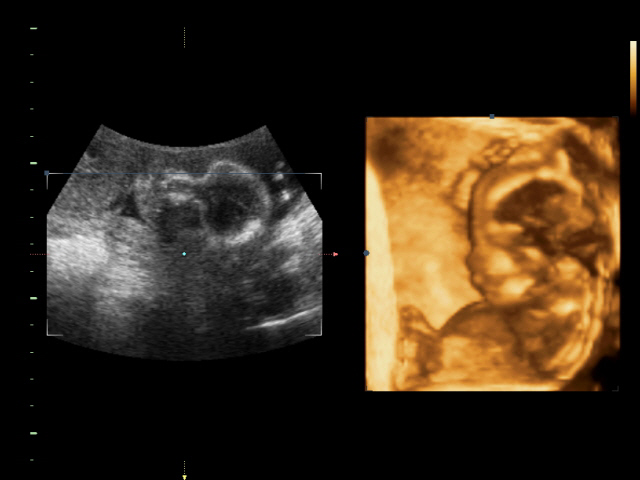

Вчера были на 4д узи... Очень понравилось))0 были всем семейством) Соня наш спал и еле показал кто он)))) как меня только не крутили-вертели... чтоб разбудить его)))) а он дрыхнет и все)))) сначала мосечку свою кулачками прикрывал. потом все таки соезволил нам показать свои губешки и курносый нос))) что-то там ротик открывал)))

а тут открыл своё личико)))